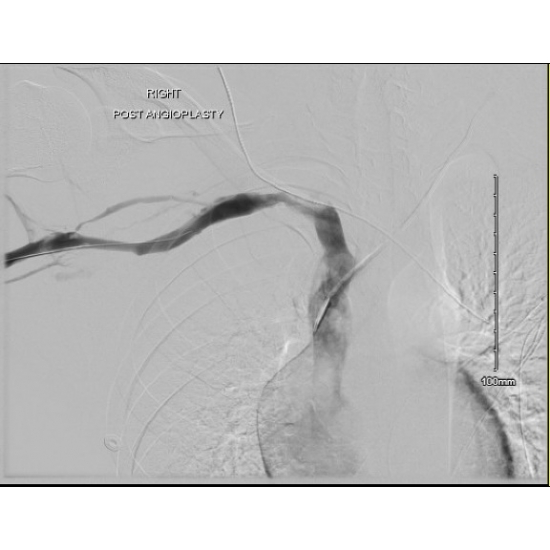

Pre-Angio Subclavian

Case Photo #5